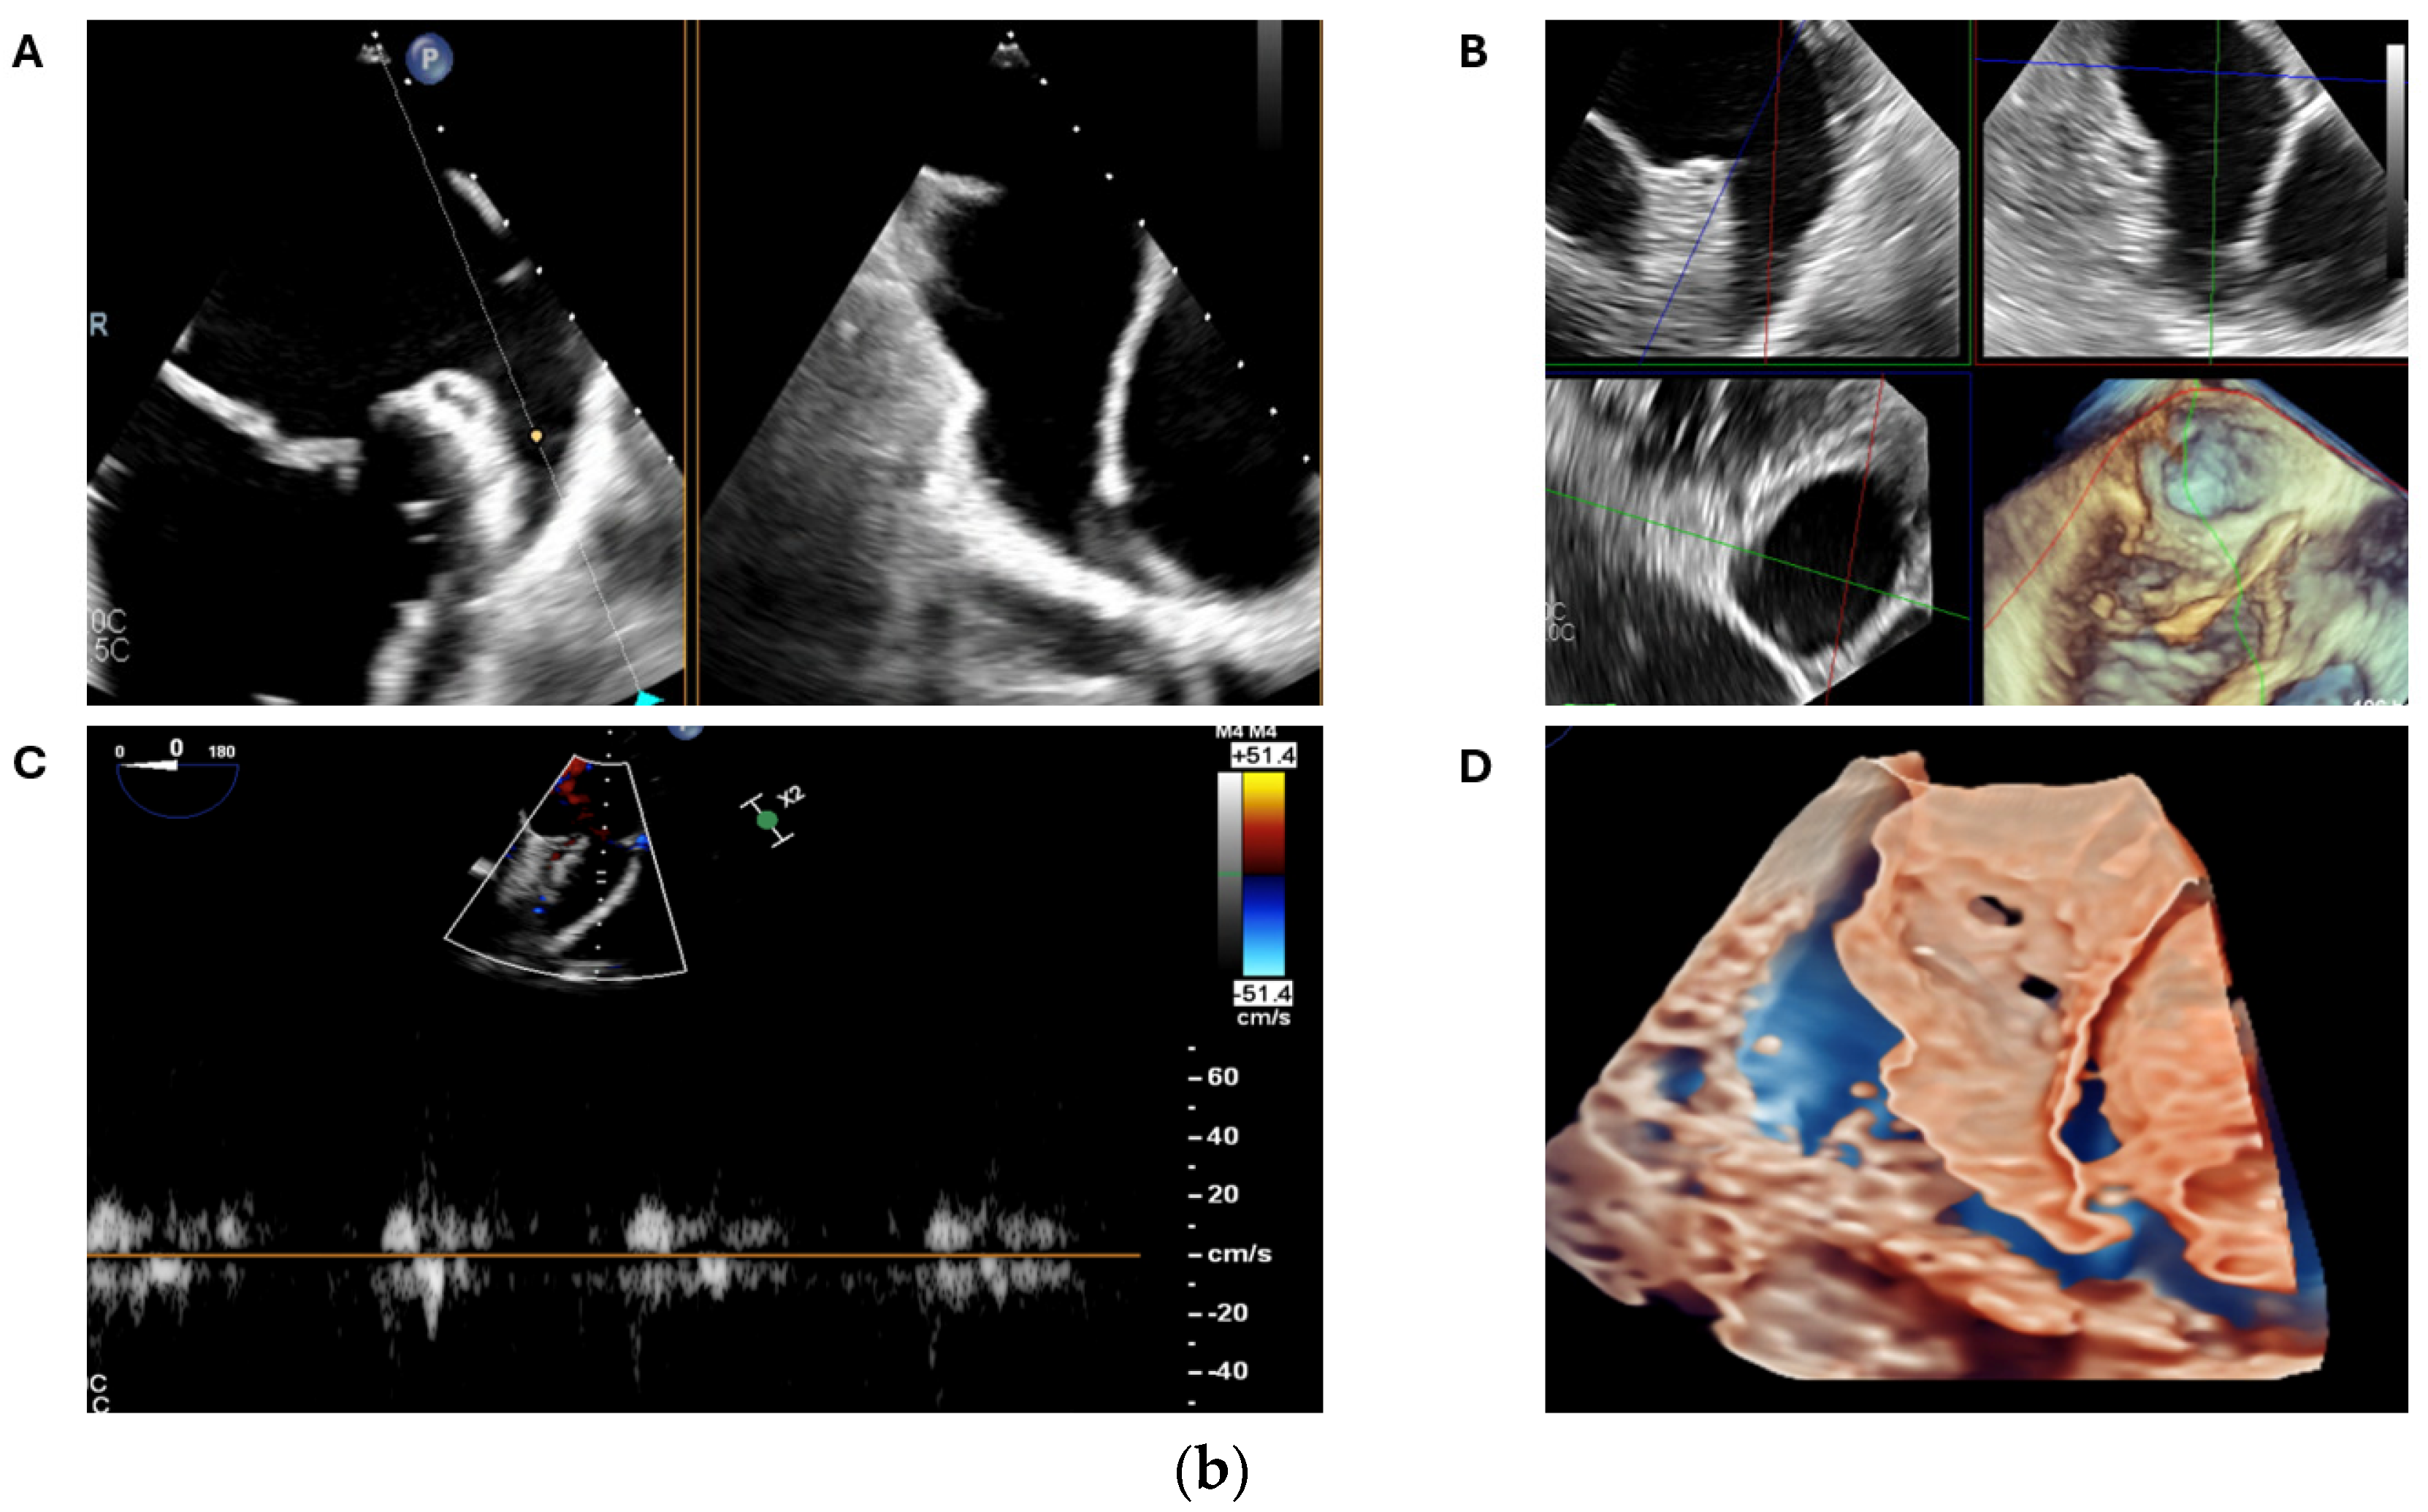

2.2.2. LAA Measurements (Anatomy and Morphology)

2.2.3. Intra-Procedural TOE